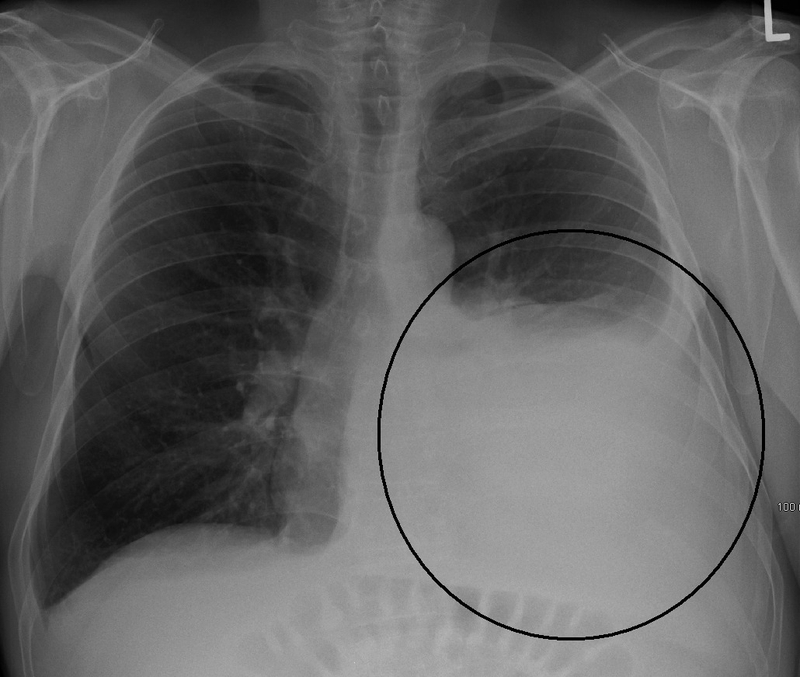

Tràn dịch màng phổi hay còn gọi là tình trạng “ứ nước trong khoang màng phổi” (Tên tiếng Anh: Pleural Effusion). Các chất lỏng trong khoang màng phổi có hiện tượng tích tụ bất thường gây nên tràn dịch màng phổi. Bình thường, lượng dịch trong khoang màng phổi chỉ vào khoảng 10 – 20 ml và nếu chúng nhiều hơn mức bình thường sẽ gây nên tình trạng tràn dịch màng phổi. Khi bị tràn dịch màng phổi, bạn có thể bị tức ngực, khó thở. Tràn dịch màng phổi do lao là dạng tràn dịch màng phổi dịch tiết.

Tràn dịch màng phổi do lao là bệnh khá thường gặp, xếp độ phổ biến thì chúng đứng thứ ba sau lao phổi và lao hạch, chiếm 25% - 37% những trường hợp tràn dịch màng phổi.